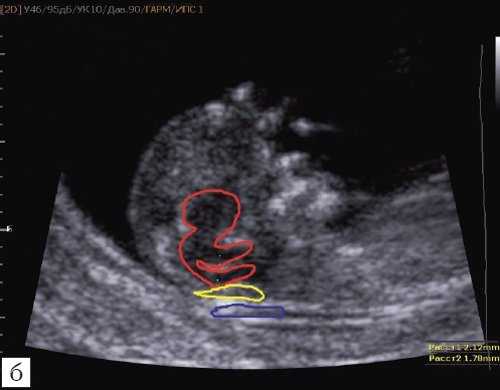

При изучении среднесагиттального скана будет отсутствовать визуализация IV желудочка и большой цистерны, а размер среднего мозга будет увеличен. Изучая "осьминожку", можно увидеть лишь одну верхнюю ножку, большого размера (увеличенный ствол мозга), а нижняя ножка (IV желудочек) - отсутствует. Также не визуализируется большая цистерна (одна из "подушек", на которой лежит "осьминожка") (рис. 5).

Отсутствие визуализации IV желудочка, большой цистерны.

Красный цвет - одноногая "осьминожка"; синий цвет - воротниковое пространство.